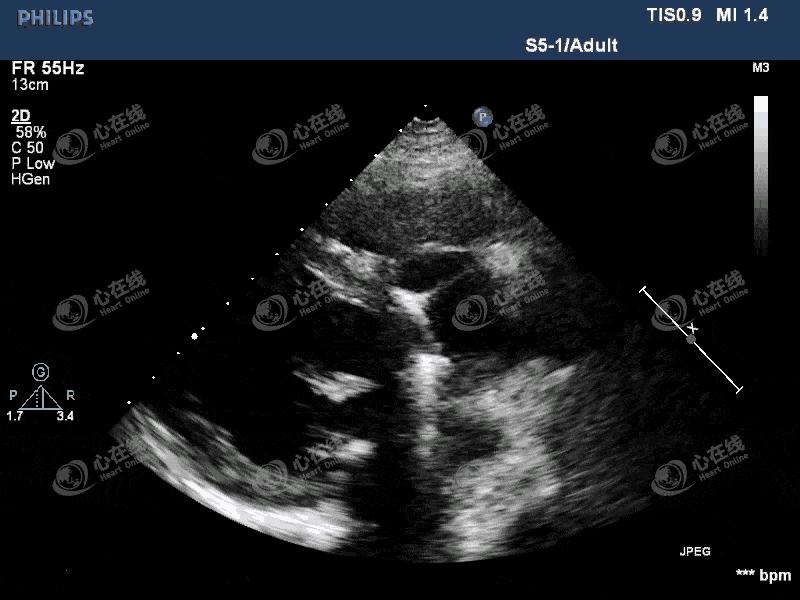

图1 左室长轴切面:左心饱满,主动脉瓣为人工机械瓣,缝合环活动度增大,主动脉根部前壁及后壁紧邻机械瓣处可见一隔膜样回声,其上可见破口,该处可见无回声区。